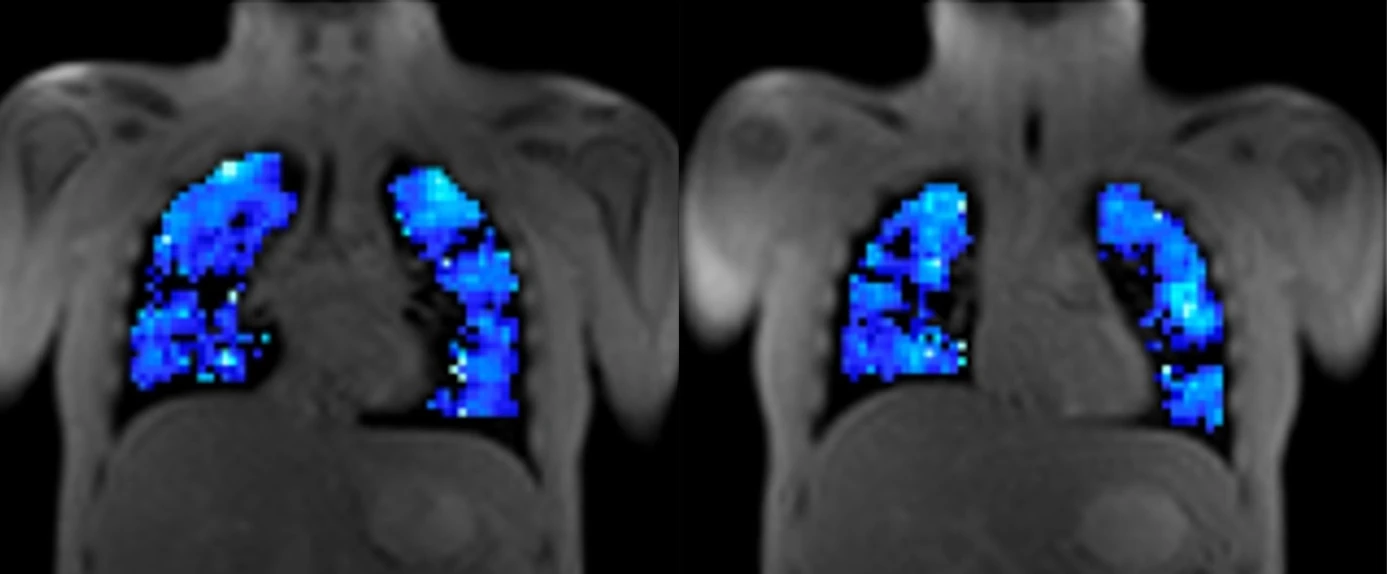

From study design to final reporting, Bioxydyn delivers repeatable MRI biomarkers that reveal tissue function, physiology and change. Our operational excellence and metrology help you compare results across sites, scanners and timepoints.

Disease areas and services supporting quantitative MRI biomarkers across clinical trials.